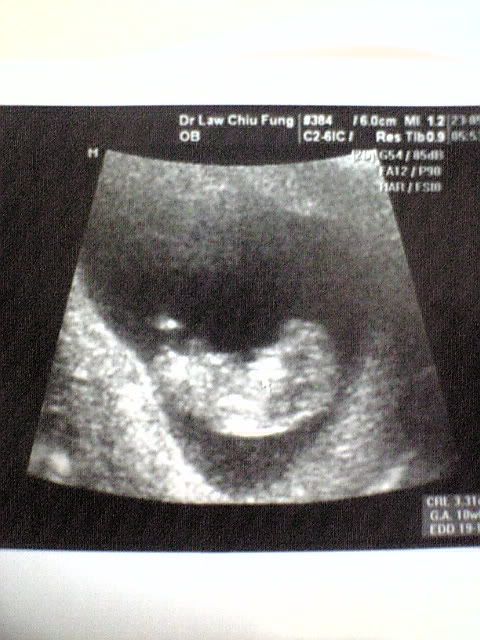

我睇左e生la,

湯丸有3.31cm呀,

size好正常....

照超聲波時週身郁腳撐撐,

e生話邊有10週bb禁百厭架tim !!

睇黎湯丸遺傳左湯氏伉儷最曳既細胞la !!!!!